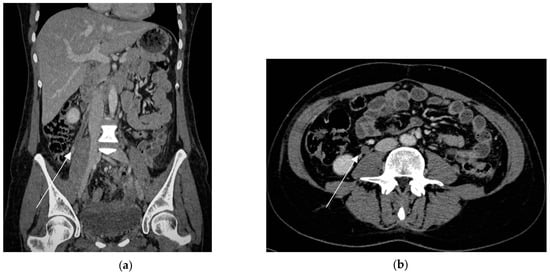

CT with intravenous contrast represents the modality of choice for the diagnosis of OVT post partum, assessing the extent of the thrombosis within the renal vein and the inferior vena cava. A thick-walled, enlarged ovarian vein with rim enhancement and an intra-luminal central filling defect are the main imaging findings of OVT [114]. Multiplanar imaging allows for the distinguishing of the thrombosed vein from the other tubular structures, such as ureters or a loop of bowel (Figure 11).

Figure 11.

Right ovarian vein thrombosis in a puerperal patient (6 days after delivery) in a 32-year-old woman who underwent hysterectomy for massive primary post-partum hemorrhage due to undiagnosed placenta percreta. Coronal portal venous phase (a) shows a low-attenuation tubular structure in the right ovarian vein (arrow) that extends up toward the inferior vena cava, representing thrombosis. Axial portal venous phase (b) depicts thrombus as a filling defect in the right ovarian vein (arrow).

In a pregnant patient, the ionizing radiation limits the employment of CT [113,114]. Non-contrast MRI can be a problem-solving tool in the clinical suspicion of OVT in pregnancy. On T1-weighted images, the ovarian thrombus can exhibit variable signal intensity depending on the age of luminal blood products, whereas on T2-weighted images, it is shown as a lack of the normal low-signal-intensity flow-void of a patent vessel [81,114]. Nevertheless, images from these unenhanced MRI sequences should be carefully interpreted, because unenhanced sequences are limited by flow signal artifacts [114]. Unenhanced MR venography performed using the time of flight (TOF) technique can depict the thrombus as a flow void in the vessel or the vessel may be completely absent, with or without a surrounding hyperintense signal intensity [3].